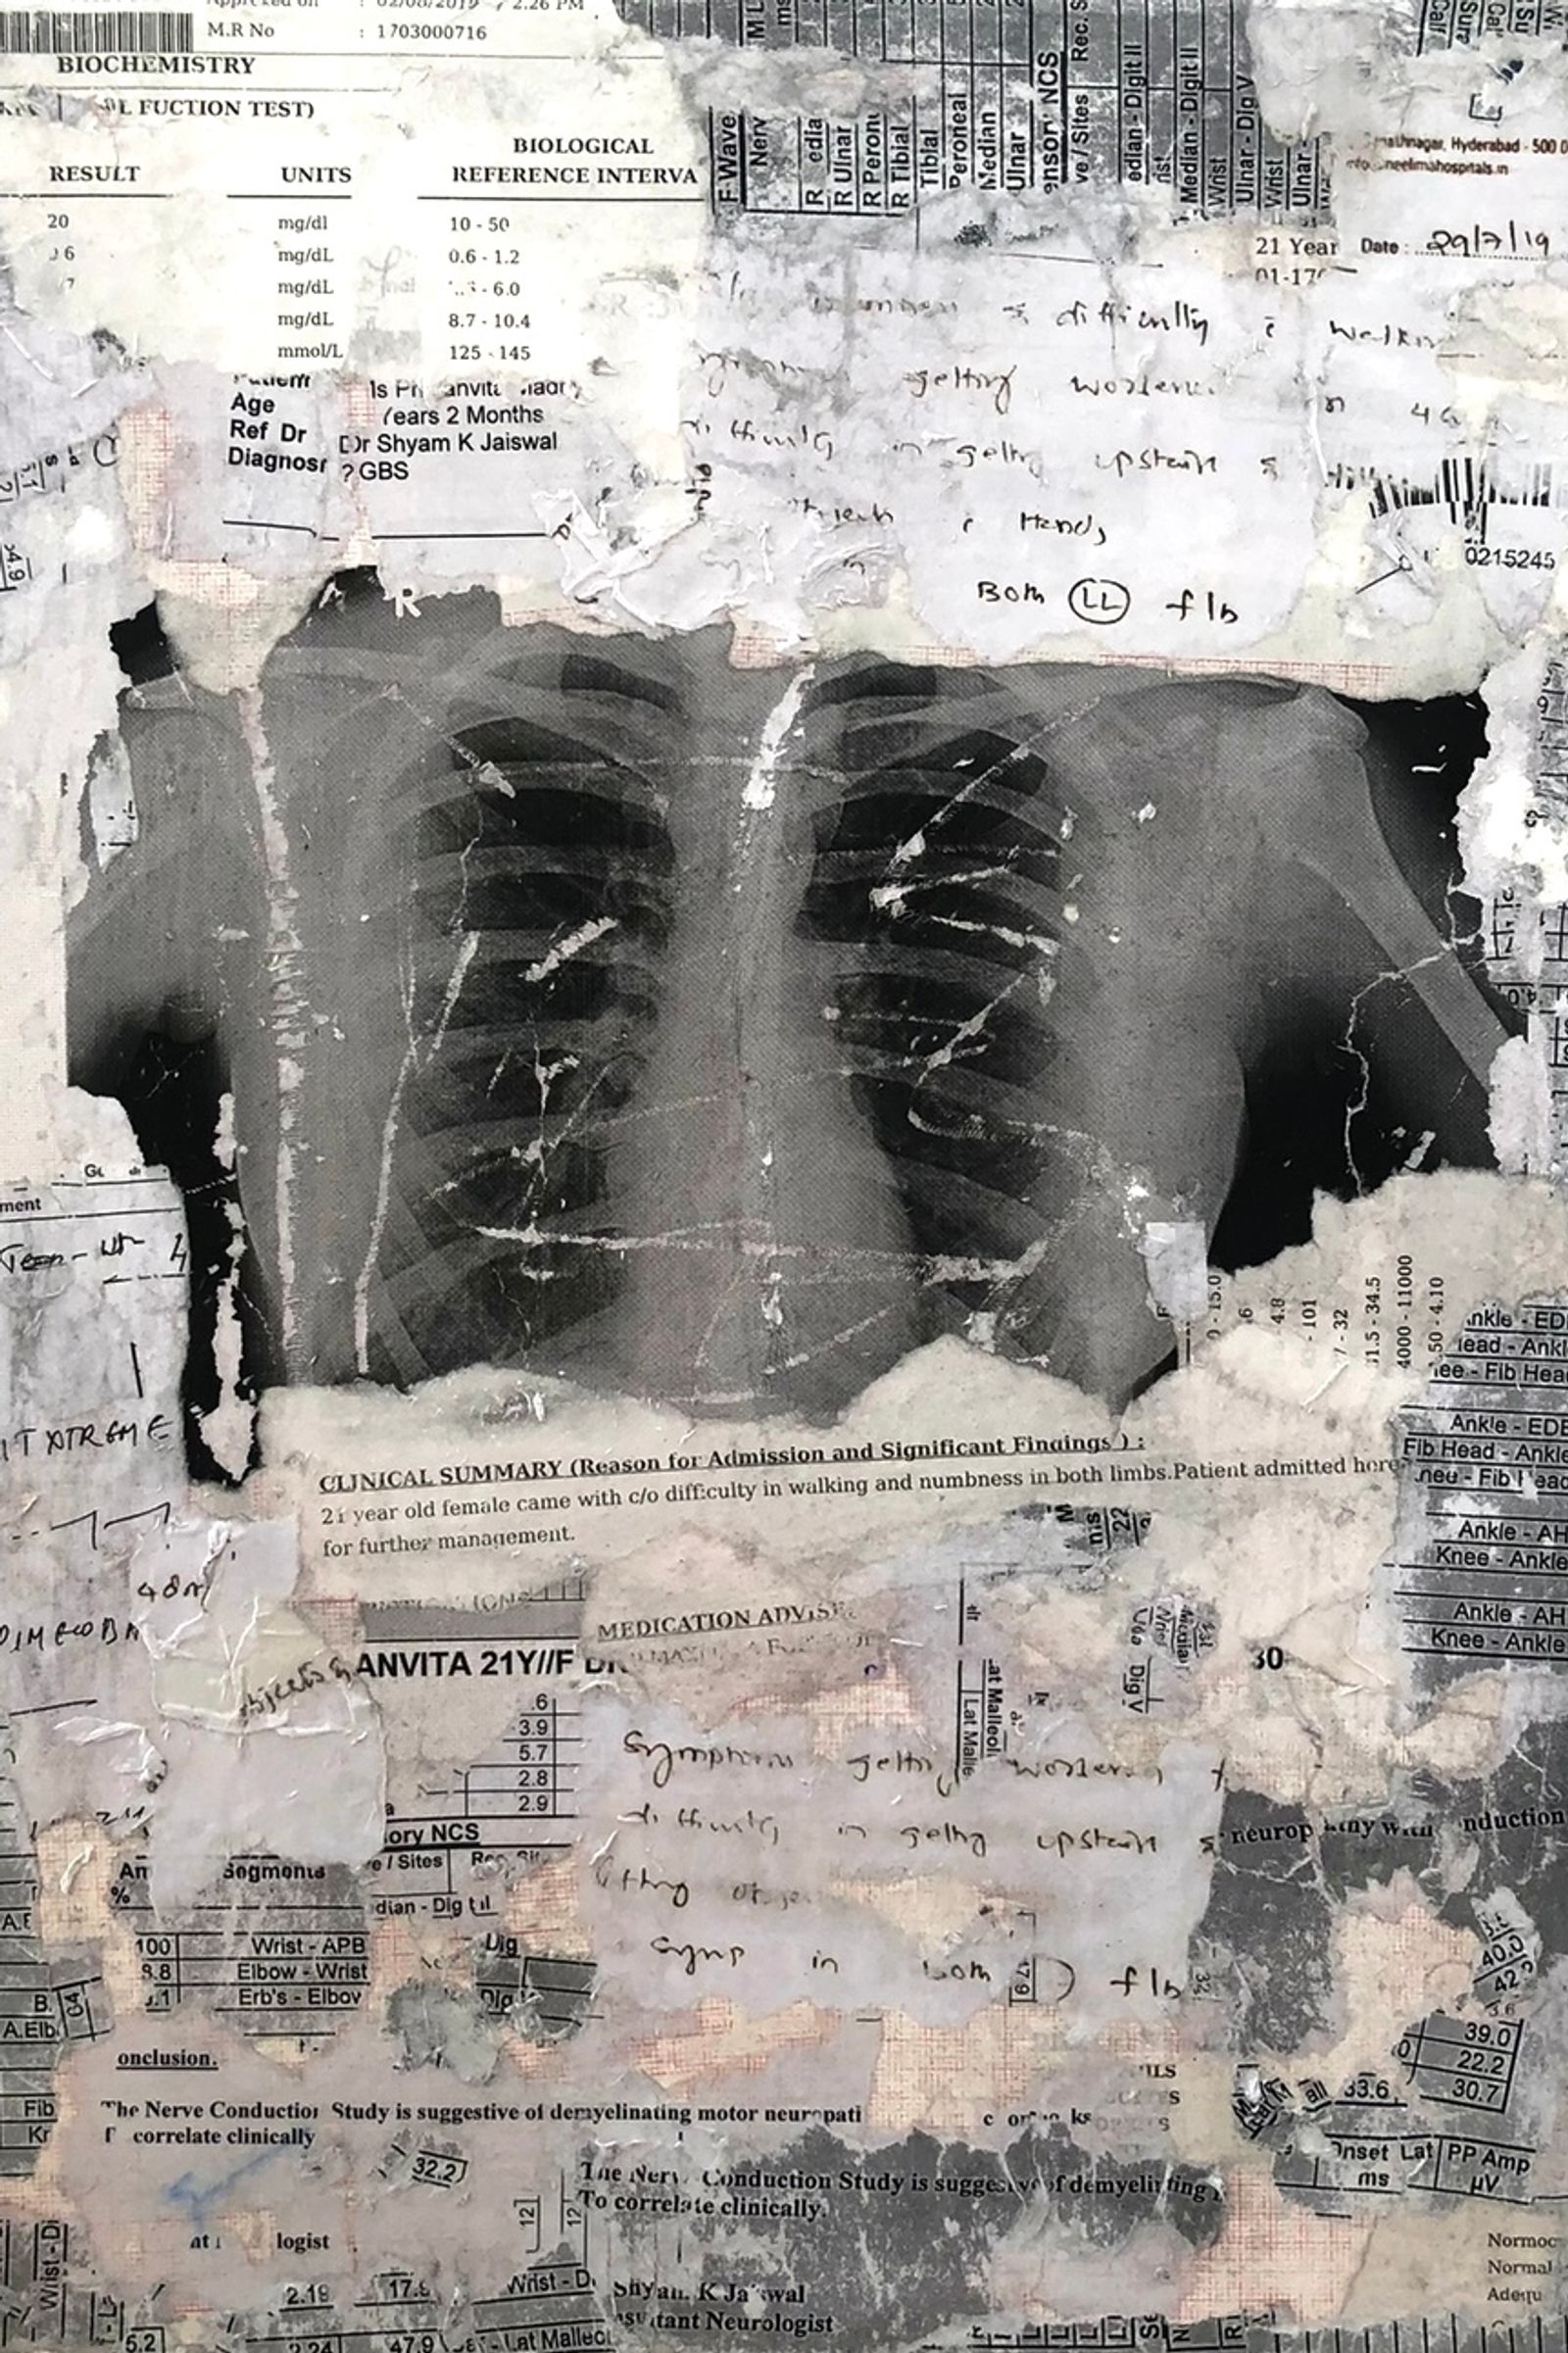

In July 2019, I was diagnosed with Guillain-Barré Syndrome, a rare neurological condition that quickly brings you to complete paralysis. Eventually, I regained movement, but I did not recover the same way inside. My body healed, yet I remained estranged from it. This disconnection between my body and soul continues to shape how I live.

There Is No Other Home emerges from the space between chaos and understanding. My body often feels like it carries its own memory. My hands loose grip, I stumble more often, and I freeze at things others take for granted, like driving. I return to fragments of memory, my mother’s CT scan when she was carrying me and my twin sister, a childhood photograph, not as evidence of illness but as traces of fragility, endurance, and survival.

During hand casting, when my fingers would not move, something happened. I felt trapped again, transported into the same helplessness of the hospital bed. My body went into shock, trembling, my fingers freezing, my breath catching, and a weight pressing down that I could neither name nor overcome. It was my body’s embodied memory in action. My body was reliving trauma beyond conscious thought, what neuroscience calls Somatic Flashback. This experience affirmed the very questions that started this project: How does the body hold memory? How does trauma fragment the self? What does healing mean when your body feels half, disconnected, or estranged from you?

In this process of self-discovery, camera became both my weapon and my shield. I reimagine Photography as a tactile language of healing, a space to witness, question, and accept the scattered parts of self. There Is No Other Home reveals the paradox of art as both a form of control and a confrontation with chaos, where making becomes a physical encounter with trauma and healing. The hands I sculpted became more than metaphors, they turned into a tangible form of trauma, making visible what is normally invisible to the eyes.